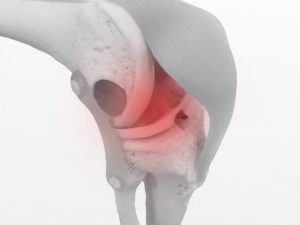

歩いたり、走ったりするときの膝の痛みでお悩みではないでしょうか。

膝の痛みの原因はさまざま考えられますが、とくに変形性膝関節症でお悩みの方が当院には多くお越しになります。

「膝の痛み」の原因

膝の痛みの原因は、股関節だとも言われています。

たとえば股関節の筋肉が硬くなり、内側に入りやすくなると「ニーイントゥーアウト」という状態になることがあります。

ニーとは膝のことで、トゥーはつま先のことです。つまり、膝が内方向を向いて、つま先が外方向を向く状態です。

「ニーイントゥーアウト」を端的に表現すると、膝がねじれた状態だと言われます。

膝がねじれた状態で走ったり、歩いたりするので膝に負担がかかり易く、炎症による痛みを伴いやすいのです。

とくに女性は股関節を開く機会が少ないため、内側に入った状態で固まってしまい、膝が痛くなりやすいとも言われています。

膝がねじれた状態で生活を続けると、膝の変形にもつながるので注意が必要です。